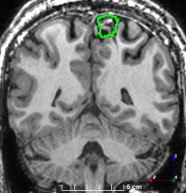

Figure 3: Manual labels from Rater A (green) and Rater D, the model trained with PubFull + EpiPre + Pseudo (magenta). Errors caused by a (a) small resection, (b) blood clot in cavity and (c) brain shift; segmentations corresponding to the (d) 50th, (e) 75th and (f) 100th percentiles giving a DSC of 81.7, 86.5 and 93.8, respectively.

Predictions errors are mostly due to 1) resection of size comparable to sulci (Fig. 6a), 2) unanticipated intensities, such as those caused by the presence of blood clots in the cavity (Fig. 6b), 3) brain shift (Fig. 6c) and 4) white matter hypointensities (Fig. 6e). Further work will involve using different internal and external cavity textures, carefully sampling the resection volume, simulating brain shift using biomechanical models, and quantifying epistemic and aleatoric segmentation uncertainty to better assess model performance [24].